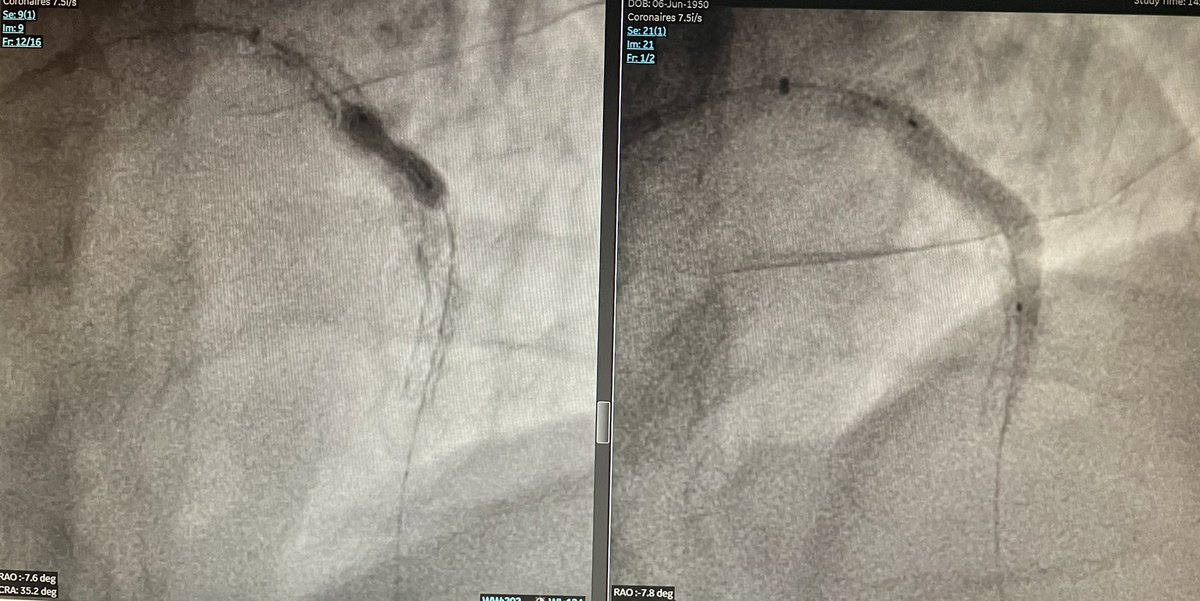

Glad for our first session of 3 Coronary Sinus Reducer cases with Pierre Barnay and Sébastien Armero at #HopitalEuropeen Marseille.

Thanks to @fra_giannini1 (our proctor) and @Neovasc team.